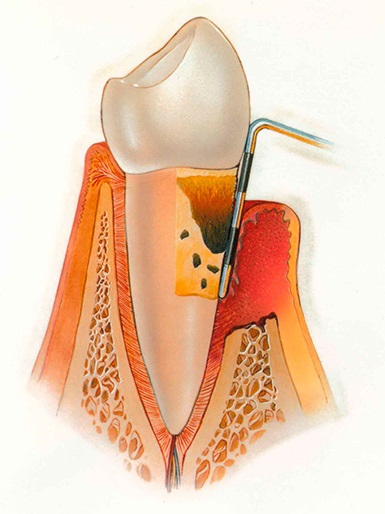

Periodontitis - olyan állapot, amikor a gyulladás eredményeként a periodontális szöveti destrukció kezdődik tooth-alátámasztó elemek, alkatrészek, kötőszövet és csont, amelyek alkotják a jól kialakított minden fog. Miután elhúzódó gyulladás vastagsága obrazovyvatsya periodontális tasakokba. És a fő oka a rombolás periodontális szövet az állandó jelenléte a fertőzés forrása a szájüregben.

Gyermekeknél a leggyakoribb oka a periodontális betegség plakk a fogak, amely eredményeként jött létre, hogy elégtelen minőségű és szabálytalan formájú. Ennek eredményeként, mikrobiális faktor okozza állandó expozíciós a mikro-organizmusok a szájüregben nyálkahártyák, az íny. És így, kezdetben gyulladt fogíny, és további gyulladást eljárást a mélyebb rétegek szövetet, és hogy közvetlenül fogágy. A periodontitis gyermekeknél összefüggésben lehet a megsértése az endokrin rendszer betegségei Az emésztőrendszer, vagy anomáliák fogászati rendszer.

Ha a fogorvos-parodontolog diagnosztizálni a fogágy gyermekek, a kezelés magában komplex eltávolítása a patogén flóra a szájüreg és a fertőzési gócok és helyreállítása, valamint a parodontális beteg periodontális szövetek. Eltávolítani egy réteg plakk a fogak felszínéről hajtjuk professzionális higiéniai takarítás és a fizikai - eljárásokat.

Jelenlétében a nagy zsebek és gyulladásos gócokat periodontális szövetek tartott fogászati egészség, majd bejuttatják a fertőtlenítő, gyulladáscsökkentő szerek. Szükségképpen károsodott fogak eltávolítása. A periodontális betegségek kezelésében gyermekeknél foglalkozó terapeuták fogorvosok, orthodontists, sebészek és periodontists óta együtt gyermekkori nagyon fontos, hogy megakadályozza a pusztítás és deformációja fogászati rendszer a szakaszban a növekedés és a képződés.

Úgy néz ki, mint a fogágybetegség gyermekeknél a fotó, ahol láthatjuk a gyulladt periodontális szövetek, íny